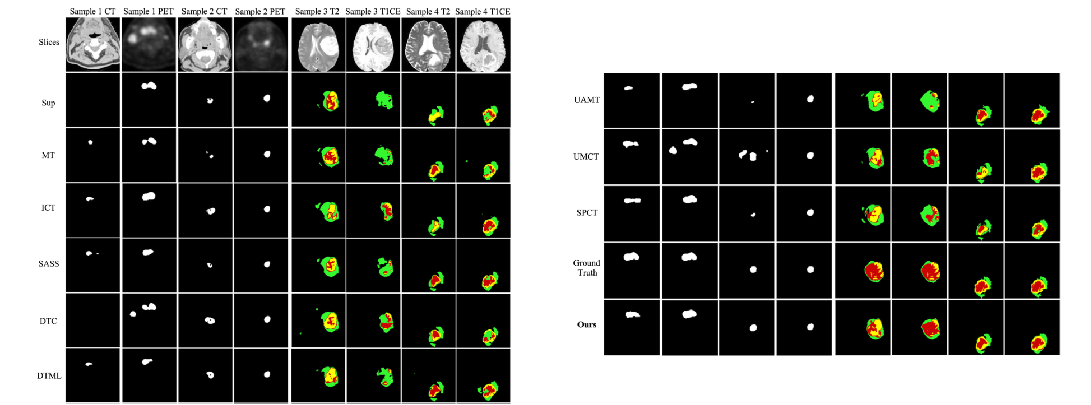

实验结果